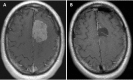

Background: Keyhole craniotomies are increasingly being used for lesions of the skull base. Here we review our recent experience with these approaches for resection of intracranial meningiomas.

Methods: Clinical and operative data were gathered on all patients treated with keyhole approaches by the senior author from January 2012 to June 2013. Thirty-one meningiomas were resected in 27 patients, including 9 supratentorial, 5 anterior fossa, 7 middle fossa, 6 posterior fossa, and 4 complex skull base tumors. Twenty-nine tumors were WHO Grade I, and 2 were Grade II.

Results: The mean operative time was 8 hours, 22 minutes (range, 2:55-16:14) for skull-base tumors, and 4 hours, 27 minutes (range, 1:45-7:13) for supratentorial tumors. Simpson Resection grades were as follows: Grade I = 8, II = 8, III = 1, IV = 15, V = 0. The median postoperative hospital stay was 4 days (range, 1-20 days). In the 9 patients presenting with some degree of visual loss, 7 saw improvement or complete resolution. In the 6 patients presenting with cranial nerve palsies, 4 experienced improvement or resolution of the deficit postoperatively. Four patients experienced new neurologic deficits, all of which were improved or resolved at the time of the last follow-up. Technical aspects and surgical nuances of these approaches for management of intracranial meningiomas are discussed.

Conclusions: With careful preoperative evaluation, keyhole approaches can be utilized singly or in combination to manage meningiomas in a wide variety of locations with satisfactory results.